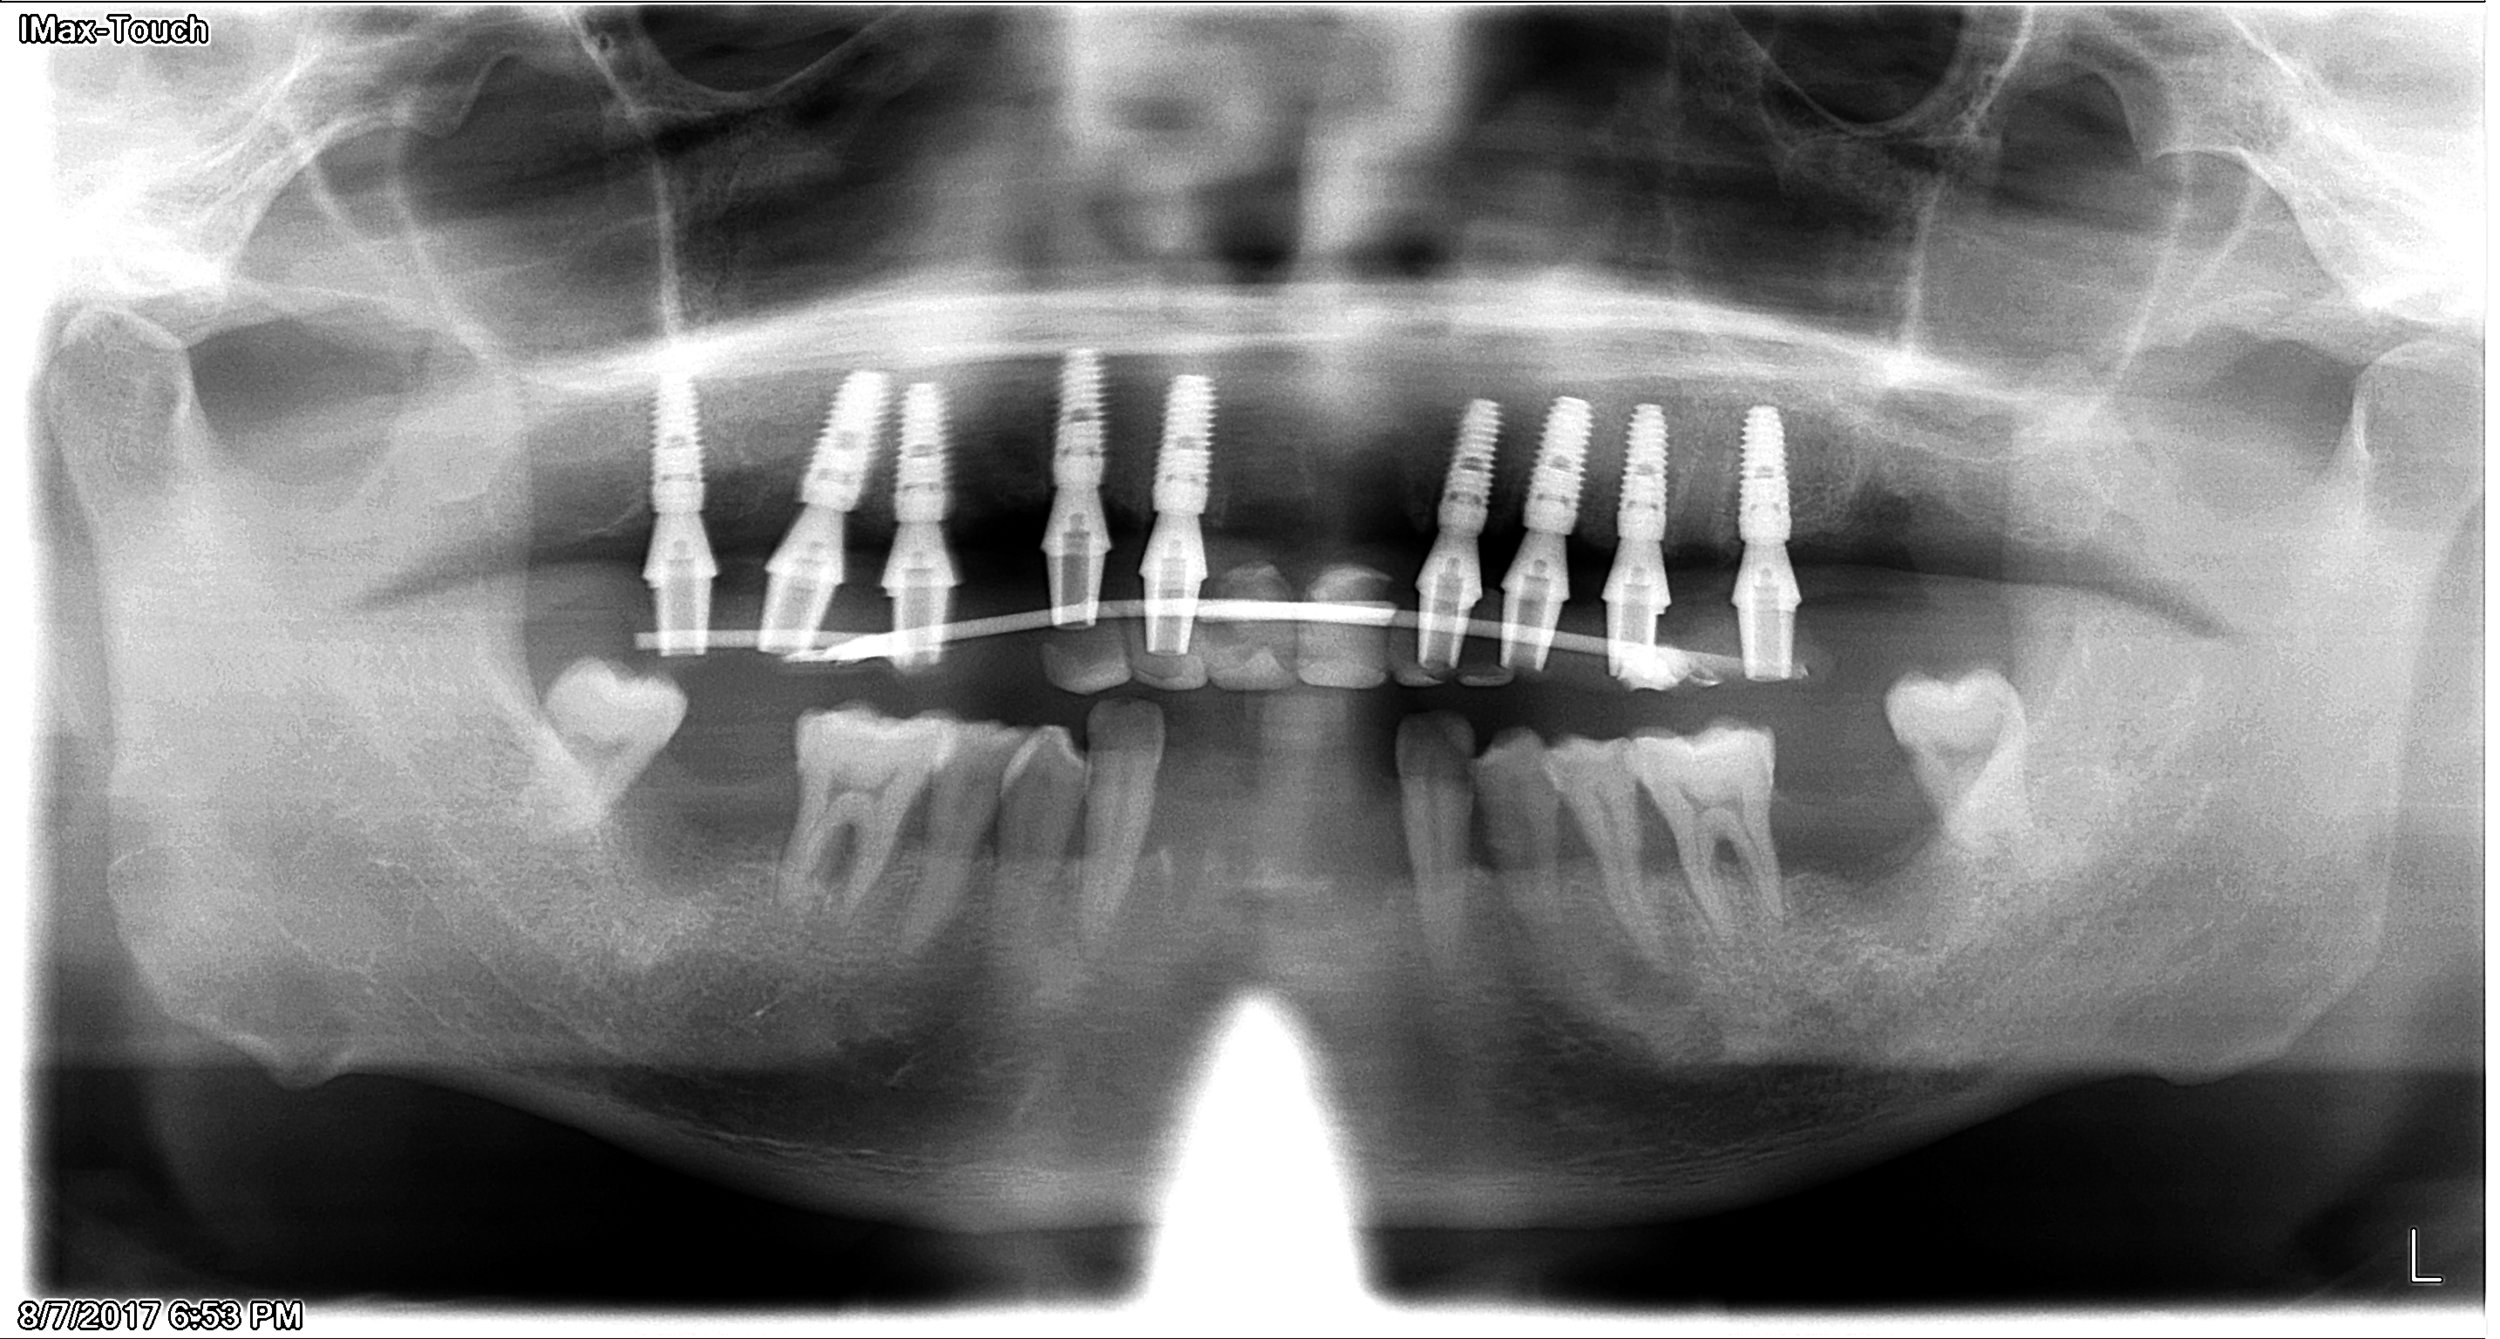

2. Surgical visits -The number of visits for the implant surgery varies depending on patient’s volume and quality of bone. We usually like to make a set of temporary so patients can ‘test drive’ the restoration.

During the surgical visit, temporary teeth (reinforced by a metal wire) is delievered the same day.

Patient in temporary phase.

Upper implant in temporary phase.